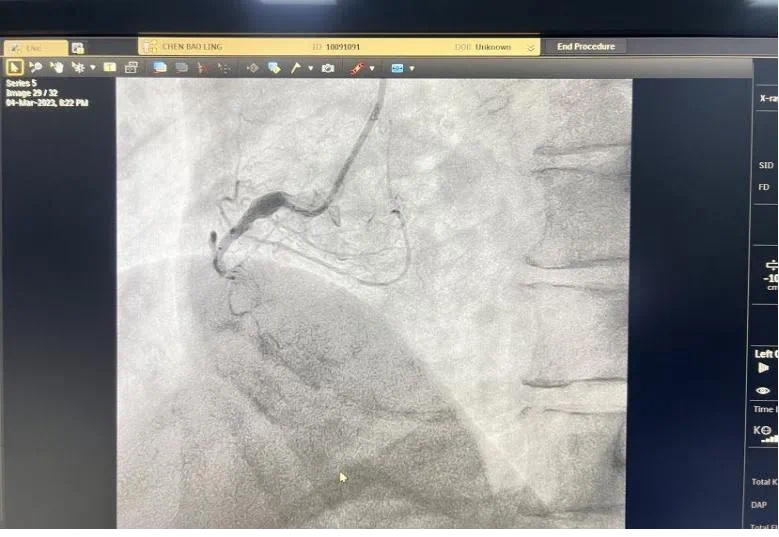

3月4号晚,总医院一个不平凡之夜。19点44分,急诊科汪小卫医生在胸痛中心微信群发送了一条信息:患者程某心电图检查结果。心内科副主任何涛马上回复:患者确诊为急性下壁ST段抬高型心肌梗塞并一键启动导管室,医生熊俊锋、导管室张梅梅立即奔赴导管室穿好铅衣备好急救药品物品,打开除颤仪做好手术准备。19点54分,激活导管室。20点08分患者被送入导管室快速实施冠脉造影,显示患者右冠近段粥样硬化伴“瘤样扩张”,中段发生完全闭塞。结合心电图考虑堵塞血管为右冠,于20点27分成功开通堵塞血管。患者从医院大门到开通血管仅50分钟,大大缩短心肌获得灌注时间,心功能基本不受影响。 术中险象环生,患者心率进行性下降,血压反复异常,经医护人员的及时救治,患者转危为安被安全护送回病房。术前、术后图片如下